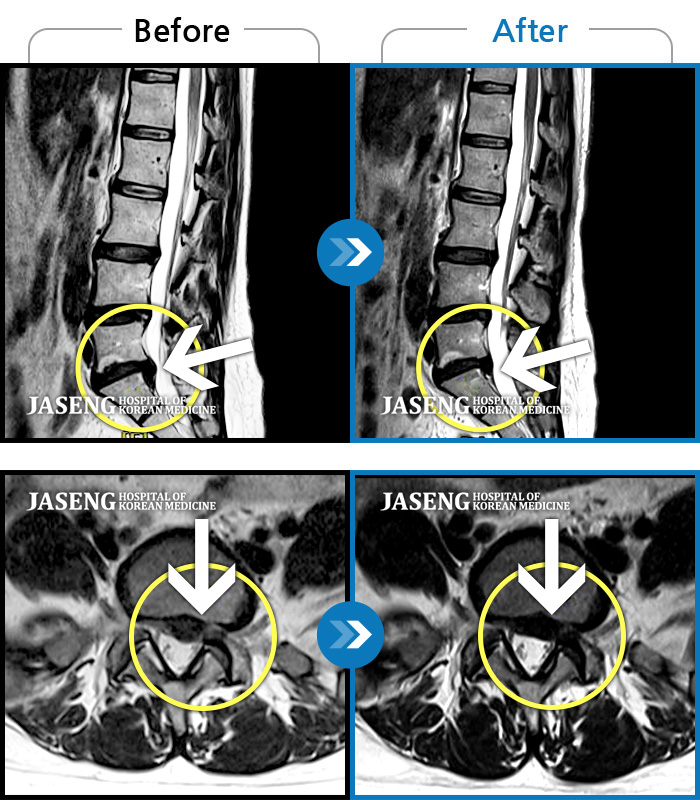

MRI 치료사례

좌측 허리부터 골반과 다리까지 이어지는 당기는 통증으로 내원하셨습니다.